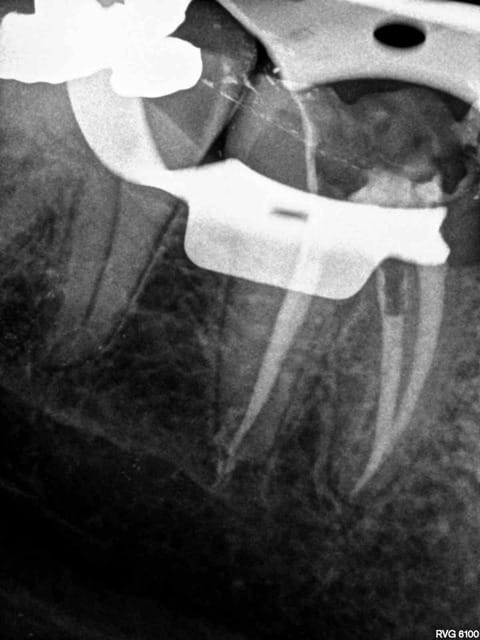

exemple :

Mobilité 31 (motif de la consultation); plan d'occlusion HS ( égression ).

Patient n'ayant pas 10 balles (mais qui travaille pourtant mais au smic malgré la moitié de cotisations sociales il a peanuts de remboursements) avec une mutuelle de merde en plus.

Amusez vous bien.

Endos + raser le secteur postérieur haut, rétablissement d'un plan d'occlusion correct avec de la fixe + Stellite bas.

Ca durera bien quelques années.

Douleur froid secteur 4. Bilan radio ( coté 6 radios, fuck le pano pas indiqué en plus source d'emmerdes-))))) détartrage.